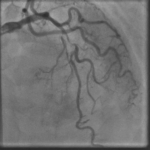

A 64-year-old man presented with angina chest pain and dyspnea on exertion. Stress MPI showed anterior, apical, and septal ischemia. Coronary angiogram revealed 2V CAD (Prox LAD CTO bifurcation with…